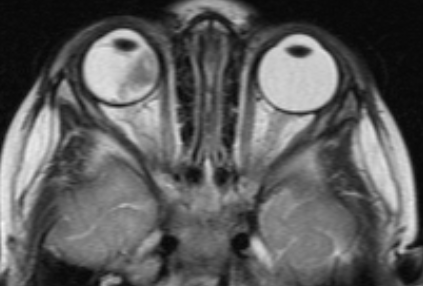

МРТ головного мозга и орбит

Магнитно-резонансная томография дает возможность в деталях увидеть распространение процесса за пределы глазного яблока и точно определить стадию болезни. Такое исследование нужно проводить всем пациентам, у которых ретинобластома диагностирована впервые. Контраст при МРТ повышает информативность.

![Визуализация ретинобластомы с помощью МРТ. Размеры образования соответствуют клинической группе D]()

Рис. 3. Визуализация ретинобластомы с помощью МРТ. Размеры образования соответствуют клинической группе D